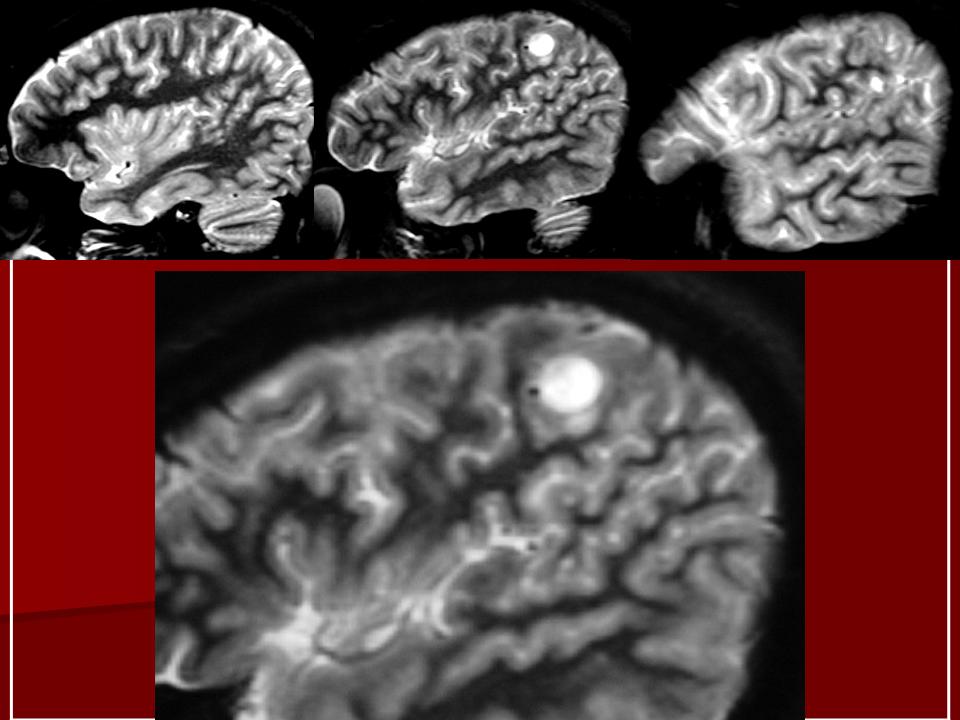

Миксоидная саркома.

1.u.slayd1_.jpg2.u.slayd2_.jpg3.u.slayd3_.jpg4.u.slayd4_.jpg5.u.slayd5_.jpg6.u.slayd6_.jpg7.u.slayd7_.jpg8.u.slayd8_.jpg9.u.slayd9_.jpg10.u.slayd10.jpg